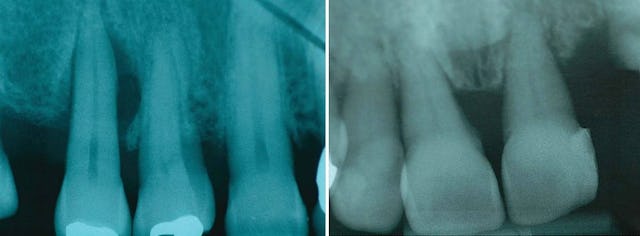

Im Bild links sehen wir einen Zahn mit sehr tiefen parodontalen Taschen. Unter und auf dem Zahnstein befinden sich immer Bakterien, welche früher oder später zu einer massiven Entzündung des Zahnfleisches und danach zu einer Entzündung des Knochens führen, in welchem der Zahn verankert ist. Der abgebildete Zahn links hat keine gute Prognose, die Tasche ist schon zu tief und eine Extraktion (Entfernung des Zahnes) wird nötig sein, da sich der Knochen nicht regenerieren kann. Alternativ wäre eine Behandlung denkbar, weil noch keine Entzündung bis zur Wurzelspitze vorhanden ist und der Zahn noch vital ist. Diese Behandlung ist allerdings sehr aufwändig und erfordert eine sehr intensive Mundhygiene seitens des Patienten und die Prognose bleibt trotzdem noch schlecht.

Die oben bereits beschriebene Entwicklung, Bakterien (Plaque) + Zahnstein, welche zur Entzündung und zum Knochenabbau führen, werden hier auf den oberen vier Bilder nochmals verdeutlicht. Auf dem dritten Bild sehen wir deutlich den Knochenabbau in der Höhe und auf dem letzten Bild den vertikalen Einbruch. In diesem Fall sprechen wir von einer schweren Parodontitis (Entzündung des Zahnhalteapparats).